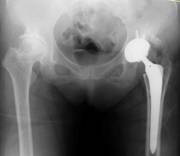

52歳 女性 両側変形性股関節症

![]() |

| 手術時間 | 83分 |

| インプラント |

|

| 設置精度 |